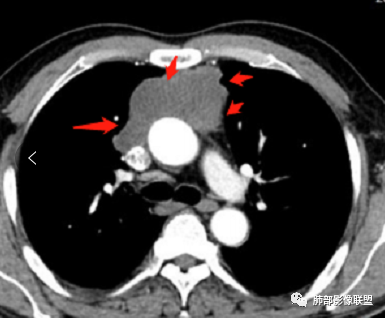

前纵隔胸腺区分叶状软组织肿块影,轻度不均匀强化,中心可见坏死,边缘不清,病灶与邻近心包见条索影,上腔静脉受侵,上纵隔多发小淋巴结,考虑胸腺鳞癌可能。

男性患者,65岁,前胸后背疼痛一个月。胸部影像:前上纵隔分叶状的软组织肿块,形态不规则,包绕大血管生长趋势,与周围分界不清,密度较均匀,呈多结节融合,肿块周围可见肿大淋巴结,内乳动脉旁淋巴结大,上腔受累,肿物内可见低密度区,增强扫描周围轻度强化。考虑:恶性病变,淋巴瘤?胸腺神经内分泌肿瘤?鉴别胸腺瘤

毛勤香:

老年男性,前纵隔肿块,形态不规则,右侧内乳动脉增粗,与血管脂肪间隙模糊消失,定性恶性,周围多发小淋巴结,有斑点状钙化灶,增强中心低密度区无强化,边缘强化为主,首先考虑胸腺鳞癌,鉴别胸腺瘤。

中老年男性,前纵隔占位,基本居中,向两侧生长;边缘膨隆分叶,部分边界不清,增强不均匀轻中度强化,坏死区边界不清;周围多发增大淋巴结,考虑恶性。主要在胸腺癌、胸腺瘤、淋巴瘤之间鉴别。病灶偏软,有钻缝样生长,这些征象偏向于淋巴瘤。但此例老年患者,病灶内有点状钙化,缺乏结节堆砌感,倾向胸腺癌诊断。